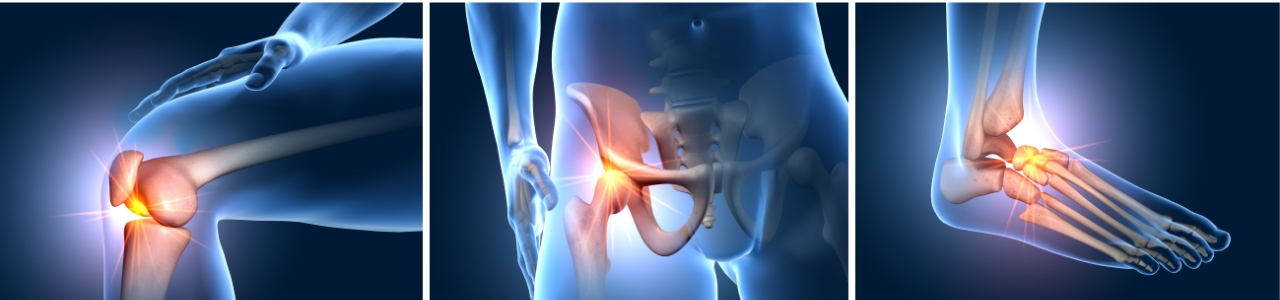

Osteoarthritis Knee Pain Relief

Joint Restoration Center (JRC) is proud to offer the Advanced Arthritis Relief…

Knee Pain Relief

Keep Your Knees In Shape With Innovative Treatment Options Including Physical Therapy!…

Ankle Pain Relief

Achieve Ankle Pain Relief in Tulsa, OK Through Physical Therapy Treatment Do…